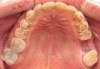

Figure 3 through Figure 7 Preoperative retracted, occlusal, and lingual views. Note the extreme acid erosion, with lost occlusal and lingual enamel.

Figure 7

When viewing his maxillary teeth from an occlusal and lingual view, one can see the erosion and wear (Figure 4, Figure 6, and Figure 7), and it becomes evident just how collapsed he actually is. This patient shows more teeth on his left side and less on the right when smiling, and the shortness and color of his teeth contributes to a definite aging of his smile. Additionally, his lips appear less full without the lip support of the lost tooth structure. The patient had Class I molar relationships on both the right and left sides, and a posterior open bite on his right side in the area of teeth Nos. 4 through 6 (Figure 8 and Figure 9). There was no crowding evident and both arches were found to have lingually inclined teeth, which may have contributed to his wear. It was also noted that his posterior teeth were worn down with a very flat anatomy and lacked proper functional guidance.